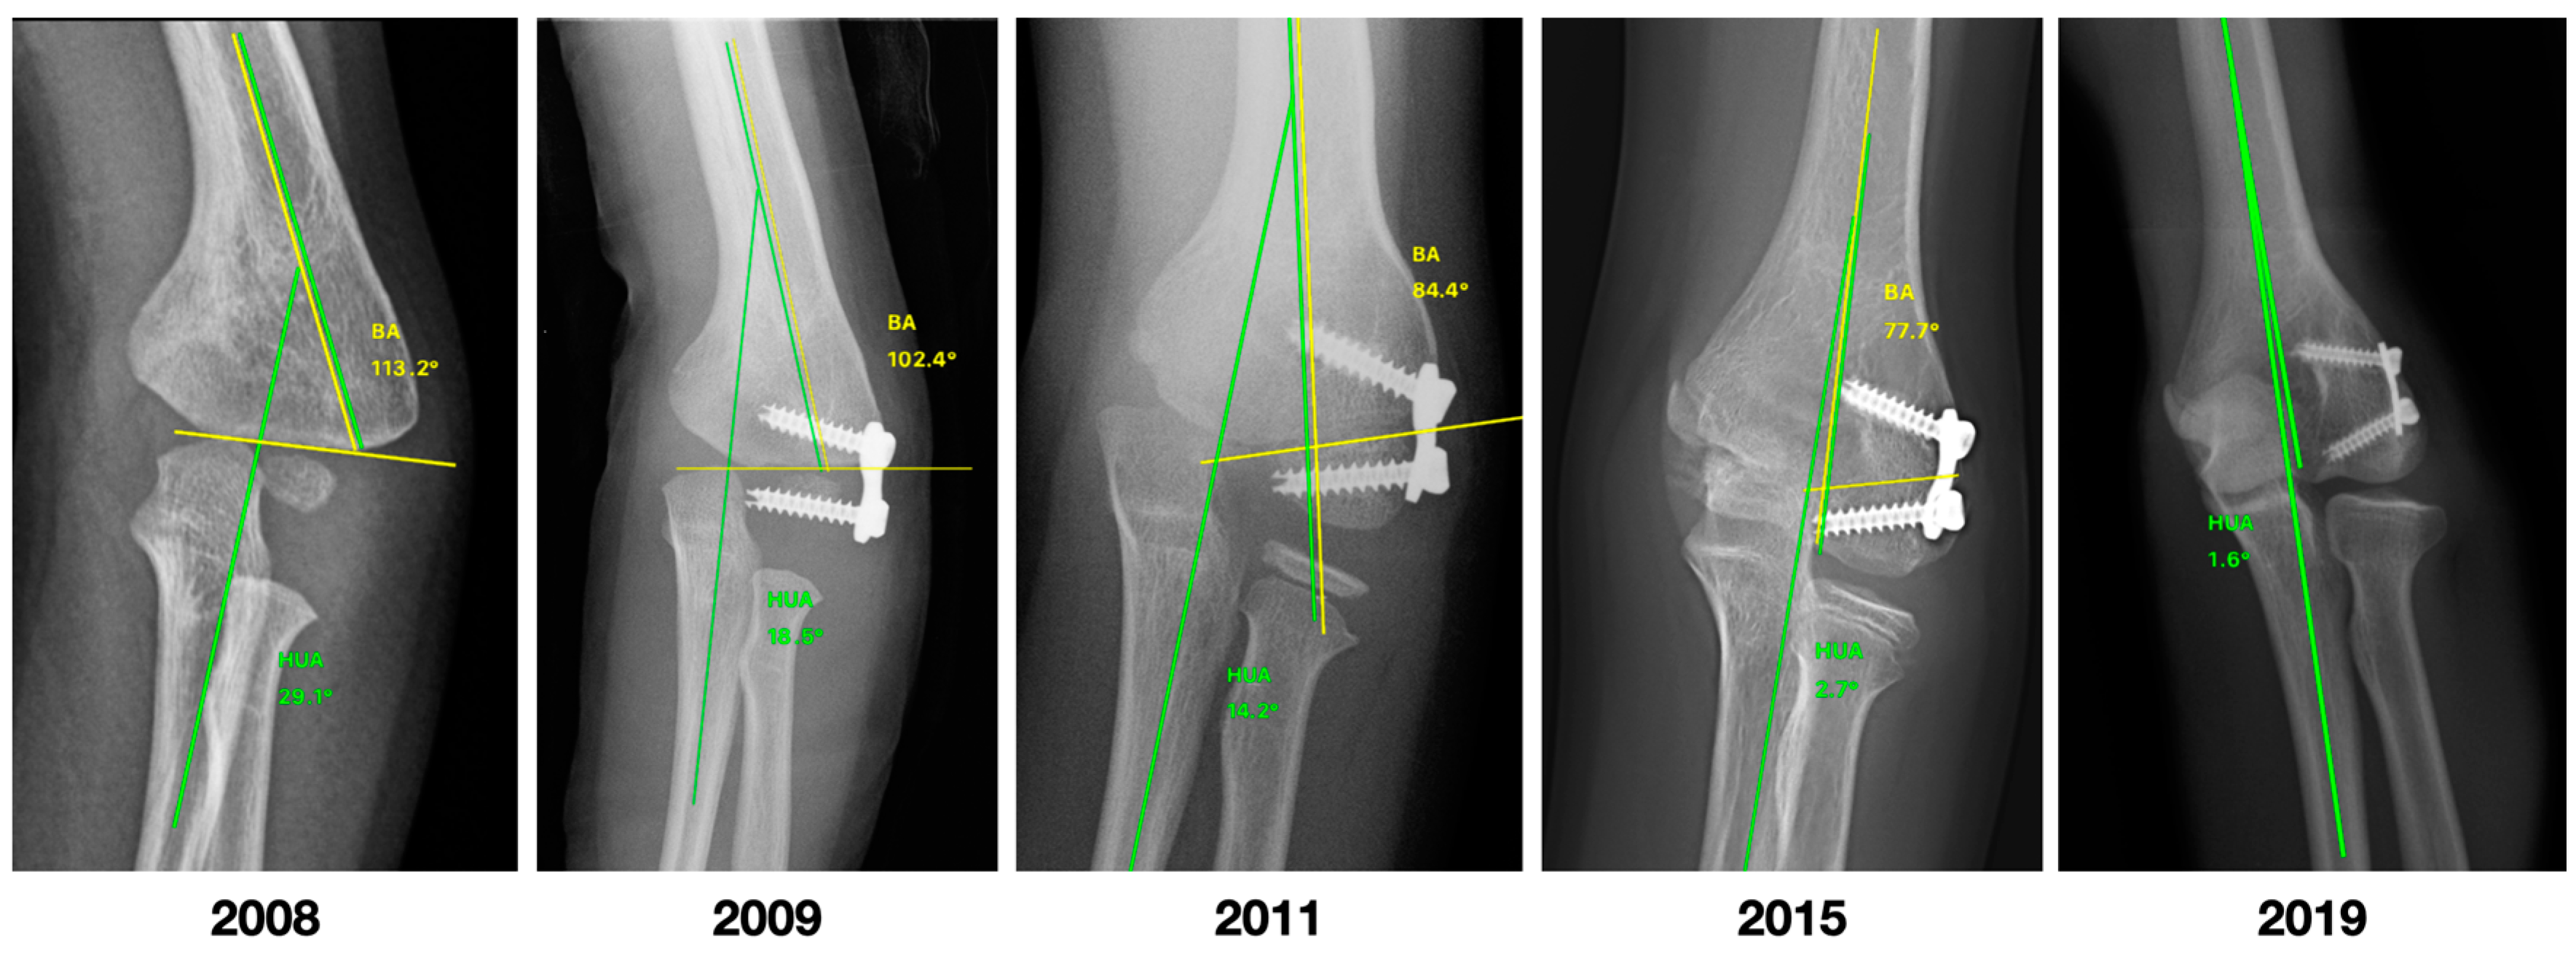

| PRE | POST | Difference | p Value | |

|---|---|---|---|---|

| CA | −20 (−18 to −26) | −6 (−4 to −9) | −16 (−18 to −9) | <0.001 |

| HUA | −19 (−15 to −29) | −8 (−1 to −10) | −16 (−19 to −12) | <0.001 |

| BA | 90 (87 to 100) | 81 (76 to 83) | −11 (−17 to −7) | <0.001 |

| SCA | 29.8 (24.3 to 36.2) | 38.5 (38.1 to 40) | 7.5 (3.3 to 13.8) | <0.001 |

| LCHA | 61.6 (54 to 64.1) | 56.7 (54.6 to 57.3) | −4.8 (−6.8 to 0.6) | 0.018 |